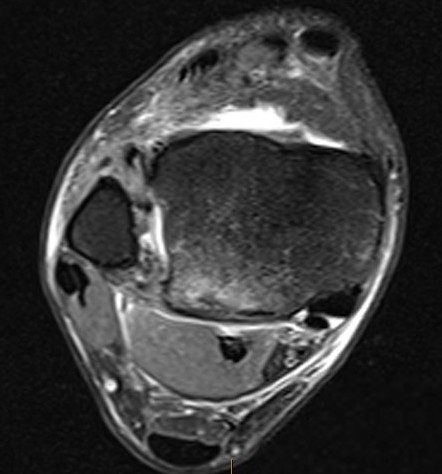

Talus ostechondral lesions

- talar dome and tibial plafond for chondral lesions

Posterior talus osteochondral lesions